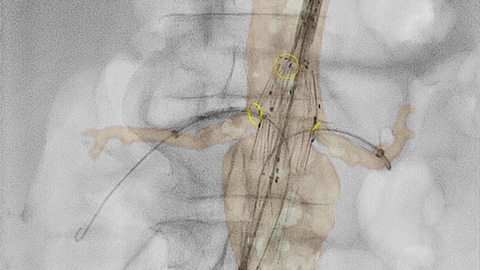

Usando a ferramenta marcador na tela sensível ao toque, você pode marcar uma área de interesse nas imagens 2D. As marcações são exibidas claramente na fluoroscopia e nas imagens de referência e podem ser ampliadas e panoramizadas junto com a imagem. Isso pode ser útil para marcar uma bifurcação, ramos laterais e outros detalhes relevantes. Com a ferramenta marcador, não há necessidade de um aplicativo de marcador separado no laboratório.